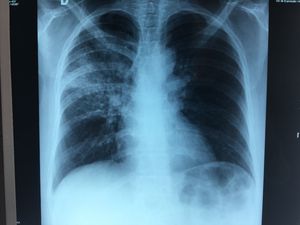

Tuberculous pneumonia

Immunocompetent patient